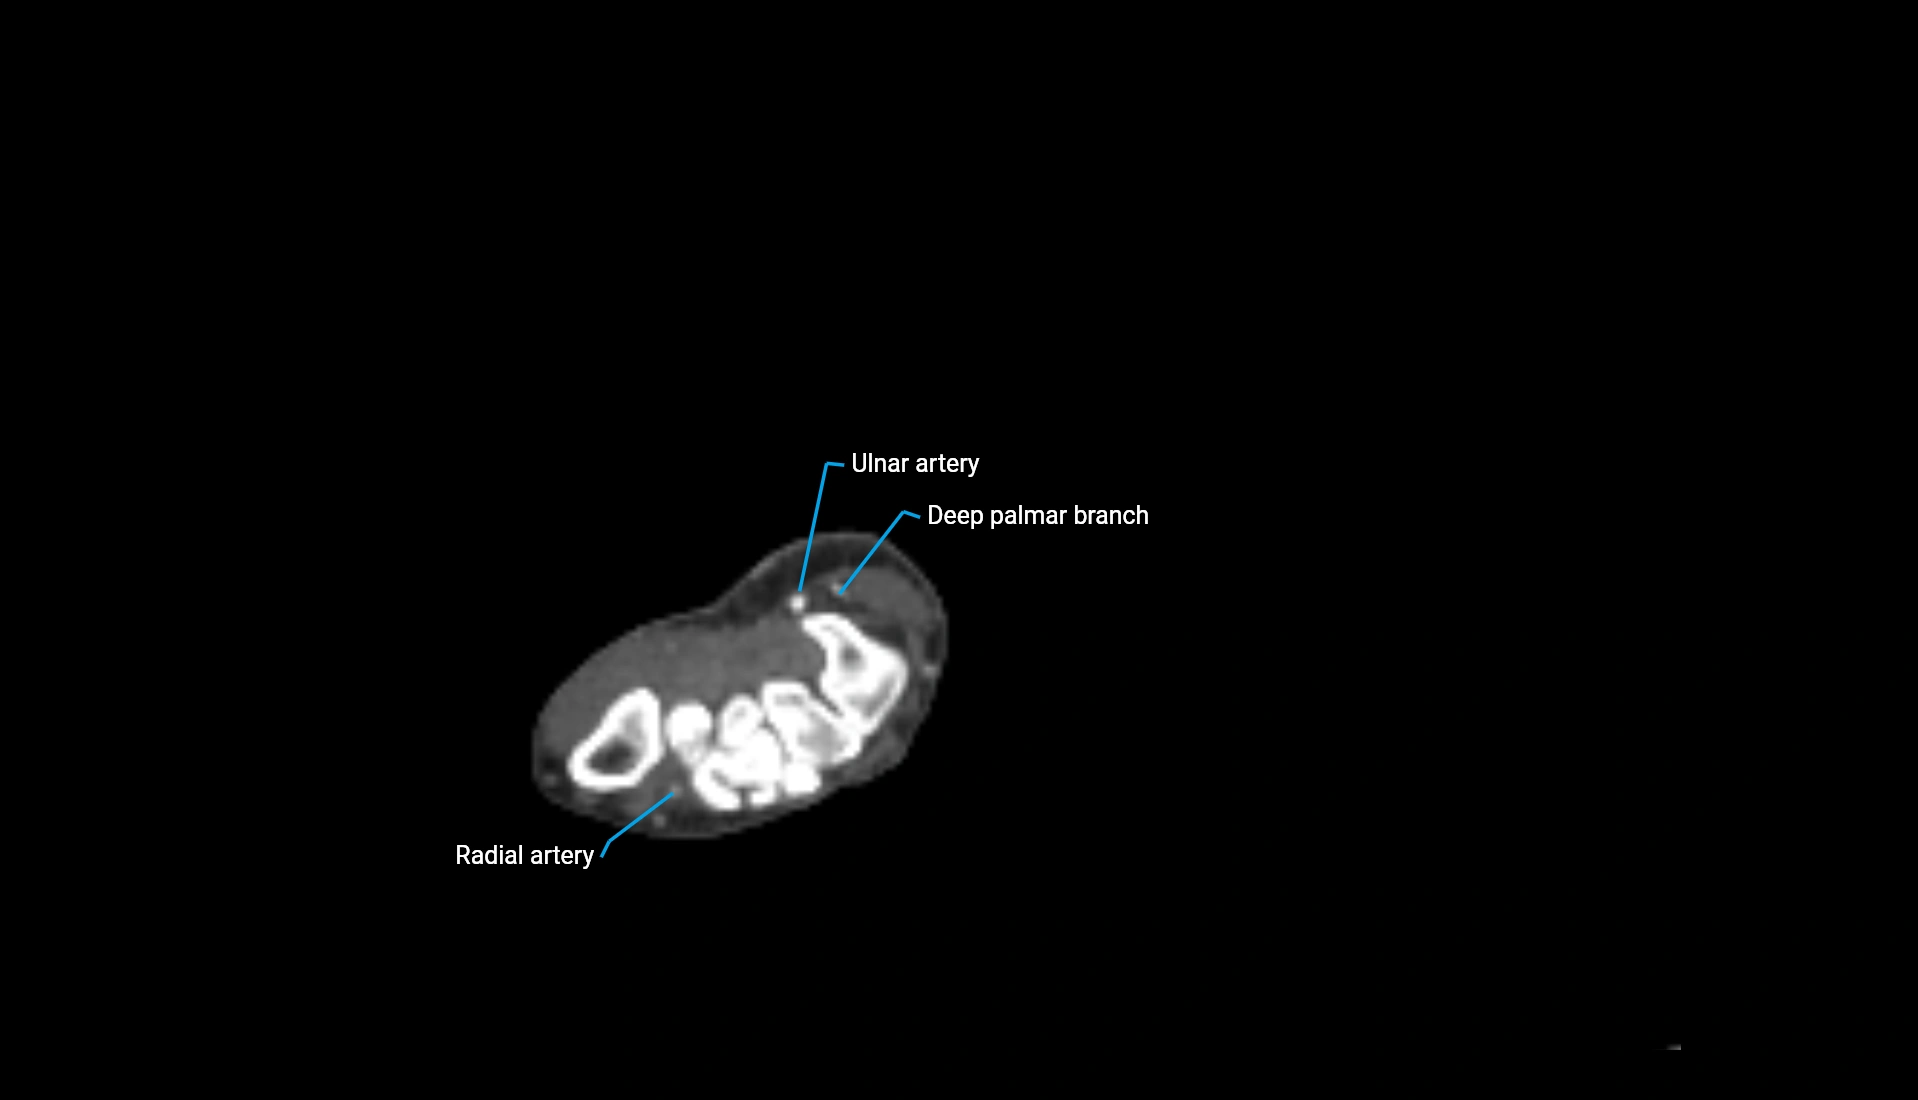

CT Appearance

Non-Contrast CT:

• Cortex: High-density, sharply defined

• Subchondral bone: Dense cancellous matrix

• Articular surface: Smooth concave contour articulating with the capitellum

• Excellent for evaluating bone integrity, alignment, and subtle fractures